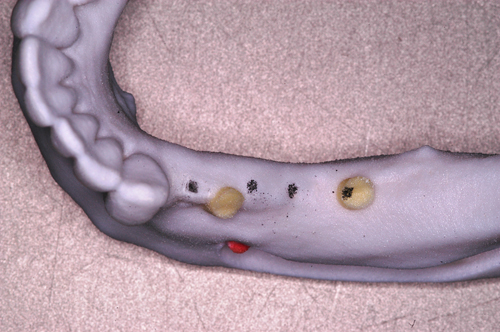

Palabras Clave: ELG: Estereolitográfico OH: Oclusión Habitual ORC: Oclusión en Relación Céntrica Paciente de 35 años de edad ,sexo masculino que lo derivan para implantar el tercer cuadrante. A la auscultación presenta ruidos articulares de tipo chasquido que remiten temporalmente luego de limitación de apertura bucal y maniobras quinesiológicas distractoras. También se observan recidivas de caries en algunos empastes y falta de disclusión canina de ambos lados. Se estudia el caso desde un punto de vista clínico, scanografico mediante Dentascan y tridimensional mediante montaje en articulador. A partir del scanner se obtienen datos para confeccionar modelo estereolitográfico (ELG),operar en el y construir férula quirúrgica dento-muco soportada. Habitualmente se procede directamente a implantar, dado que ese era el requerimiento del profesional derivante y el deseo del enfermo. Sin embargo, esa actitud enmascararía otro tipo de problemas que la boca presenta. Se consulta al odontólogo derivante, y coincide con mi opinión acerca de que si solo se lo implanta, sin corregir la posición mandibular, la situación de las ATMs, los empastes sin anatomía y la falta de disclusiones, el resultado final no será el deseado y su eficacia masticatoria no funcionará optimamente. Consultado el paciente coincide y acepta ese concepto y entonces procedemos a confeccionar un Jig de Lucia a partir del montaje de estudio, y lo dejamos puesto en boca toda la noche anterior a la consulta, para proceder a realizar un ajuste oclusal al día siguiente sin engramas anteriores, lo que facilita no tener que relajar nuevamente con laminillas de Long. En esta etapa pierde el implante correspondiente a la pieza 4.7 que traía en boca. Estabilizado el sistema, procedemos a la parte quirúrgica, comenzando por instalar la férula, retirar opérculos gingivales mediante bisturí circular, fresado óseo e instalación de implantes ,toma de impresión a cubeta fenestrada (pegando con metacrilato sin cambios dimensionales, los transfers a la cubeta especialmente diseñada.(1º método de pasividad protética utilizado), e instalación de tornillos de cicatrización. Inmediatamente de retirada la cubeta de boca y colocadas las réplicas de los implantes, procedemos a ferulizar los “ápices” de las réplicas para que no sufran movimientos durante el llenado de la impresión.(2º método de pasividad protética utilizado). Controlamos radiograficamente Tres meses después, procedemos a tomar nuevos registros de arco facial, registros intermaxilares en Oclusión en Relación céntrica, montaje de los modelos obtenidos intra operatoriamente y confección de un conjunto de cuatro coronas provisionales de metacrilato en el sector implantado y las correspondientes al maxilar superior. Verificada la perfecta función de todos los componentes, ausencia de todo tipo de síntoma y comprobada la paz en todo el sistema, procedemos tiempo después a confeccionar las fundas definitivas, que constituyen el “cerrojo” de la dinámica del mismo. Por último, corroboramos la oclusión fundamentalmente en lo que hace a la: